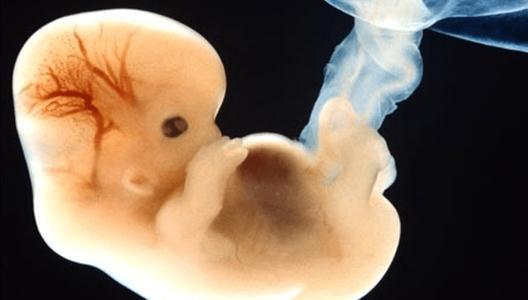

阴道B超比腹部B超早1周左右发现卵黄囊及胚芽,能尽早核实孕周、判断胚胎发育情况,在孕早期时,当有些准妈妈当听到要做阴道B超检查时,心里就开始担忧:这个检查是否会引起流产?

1.可明确孕囊的位置、胚胎的数目,观察胎芽的长度和是否有胎心搏动,如没有见到胎心搏动,要考虑是否存在胚胎停育。

2.要查看胚胎是否在宫内妊娠,葡萄胎等疾病,异常早期妊娠特别是异位妊娠(即“宫外孕”),由于宫外孕是临床急症,抢救不及时亦致死亡。

3.子宫有无肌瘤、畸形,卵巢是否正常等,之所以不采用腹部B超,是因为在孕早期(1-3个月)时,子宫还不算太大,腹部B超看得不太清楚,而这个时候进行做阴超,子宫及附件的一些问题不容易被遗漏,一旦发现异常,可以采取及时有效的处理。